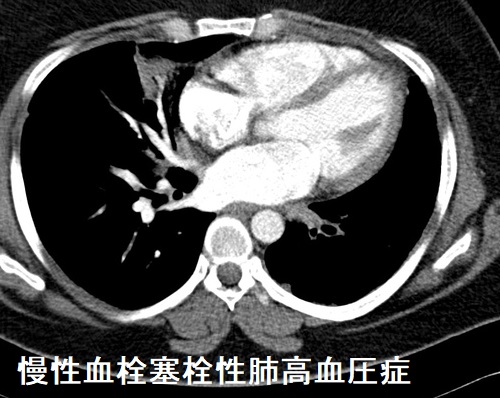

肺高血圧症(慢性血栓塞栓性肺高血圧症)のCT所見は、

- 肺動脈拡大・右心系の拡張

- 斑状のすりガラス影(モザイクパターン)、高吸収域では末梢血管影が目立つ